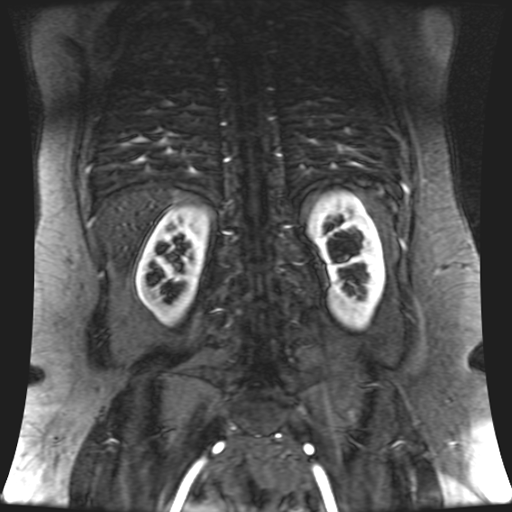

Paciente de sexo femenino, de 45 años de edad, refiere infecciones urinarias a repetición, no hay dolor, no refiere trauma, consulta por ardor al orinar, medico tratante le solicita resonancia abdominal, con énfasis en riñones, además un estudio de angiorenal.

Se prepara a paciente para ingreso a zona 4 del área de resonancia. Se coloca a paciente en decúbito supino, se canaliza en vena antecubital, se utiliza bobina de abdomen de 16 canales, se adquieren localizadores en tres planos, luego se procede a adquirir imágenes en diferentes planos, con secuencias echo spin y eco de gradiente, potenciadas a T1 y a T2.

Los sistemas colectores del riñón derecho y del riñón izquierdo, muestran alteración de sus calices primarios y secundarios, mostrando dilatación, la pelvis renal y el uréter se observan de características normales lo que indica que no hay proceso obstructivo.

Se observa dilatación del sistema calicial sin proceso obstructivo compatible con una anormalidad del desarrollo de los sistemas colectores de ambos riñones, definiéndose como una “megacaliosis”

La megacaliosis congénita es una anomalía del desarrollo del sistema colector renal caracterizada por una dilatación homogénea de los cálices renales, sin dilatación de la pelvis ni del uréter y sin obstrucción demostrable. Se considera una malformación del sistema colector más que una uropatía obstructiva en sentido estricto.

Desde el punto de vista anatómico e histopatológico, la mayoría de los autores coinciden en que la base de esta anomalía es un desarrollo anómalo de la médula renal: hay hipoplasia de las pirámides medulares, papilas renales malformadas o aplanadas, y acortamiento de los túbulos colectores, lo que se traduce en cálices más numerosos, ensanchados y de contornos facetados o “en trébol”.